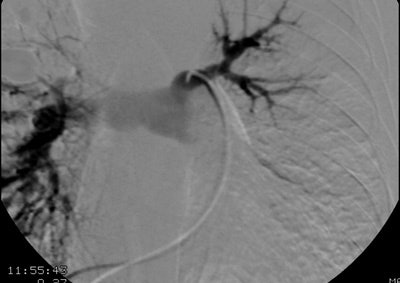

Selective left pulmonary arteriogram revealed the vessel to be patent, although irregular and narrowed. A delayed run was not performed, but the findings were felt to be consistent with pulmonary venous obstruction based upon the CT scan findings.